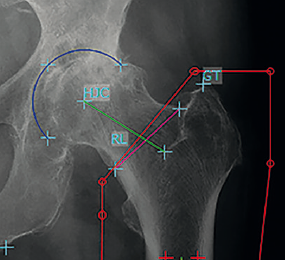

5. Xác định chênh lệch offset của xương đùi hai bên

Các thuật toán đo lường mới với sự hỗ trợ của máy tính đã được thiết lập để hỗ trợ bác sĩ phẫu thuật trong quá trình thay toàn bộ khớp trong mổ. Bác sĩ có thể đánh giá chiều dài chân và độ lệch được đo bằng hệ thống định vị đáng tin cậy trong quá trình tạo hình khớp háng .

Ước tính đền bù xương đùi. Độ di lệch xương đùi được định nghĩa là khoảng cách giữa trục dọc ở giữa của xương đùi đến tâm xoay của khớp háng.

6. Xác định chênh lệch offset của ổ cối hai bên

Mức độ chính xác của cỡ số ổ cối theo tỷ lệ phóng đại X quang từng trường hợp . Đánh giá mức độ chính xác của cỡ số ổ cối theo tỷ lệ phóng đại trung bình. Khoảng chênh lệch từ tâm xoay đến đường thẳng đứng đi qua góc dưới xương ổ cối cùng bên so với bên lành.